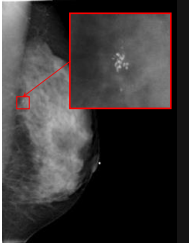

「マンモグラフィ」は乳腺のX線検査です。乳がんをはじめ乳房にできる病気をほとんど見つけることができ、しこりとして触れないごく早期の乳がん(微細な石灰化)も発見できます。 X線を使いますが、その量はごくわずかでほとんど危険はありません。

乳房を圧迫しながら薄く均一に広げることによって、乳房内をより鮮明に見ることができます。触ってもわからないような早期の小さながんや、非常に小さな石灰化*をみつけることができます。(*石灰化があるからといって必ずしも悪性とは限りません)

マンモグラフィでは、触診ではわからない小さながんを発見できます。

マンモグラフィによる腫瘤(左)と石灰化(右)